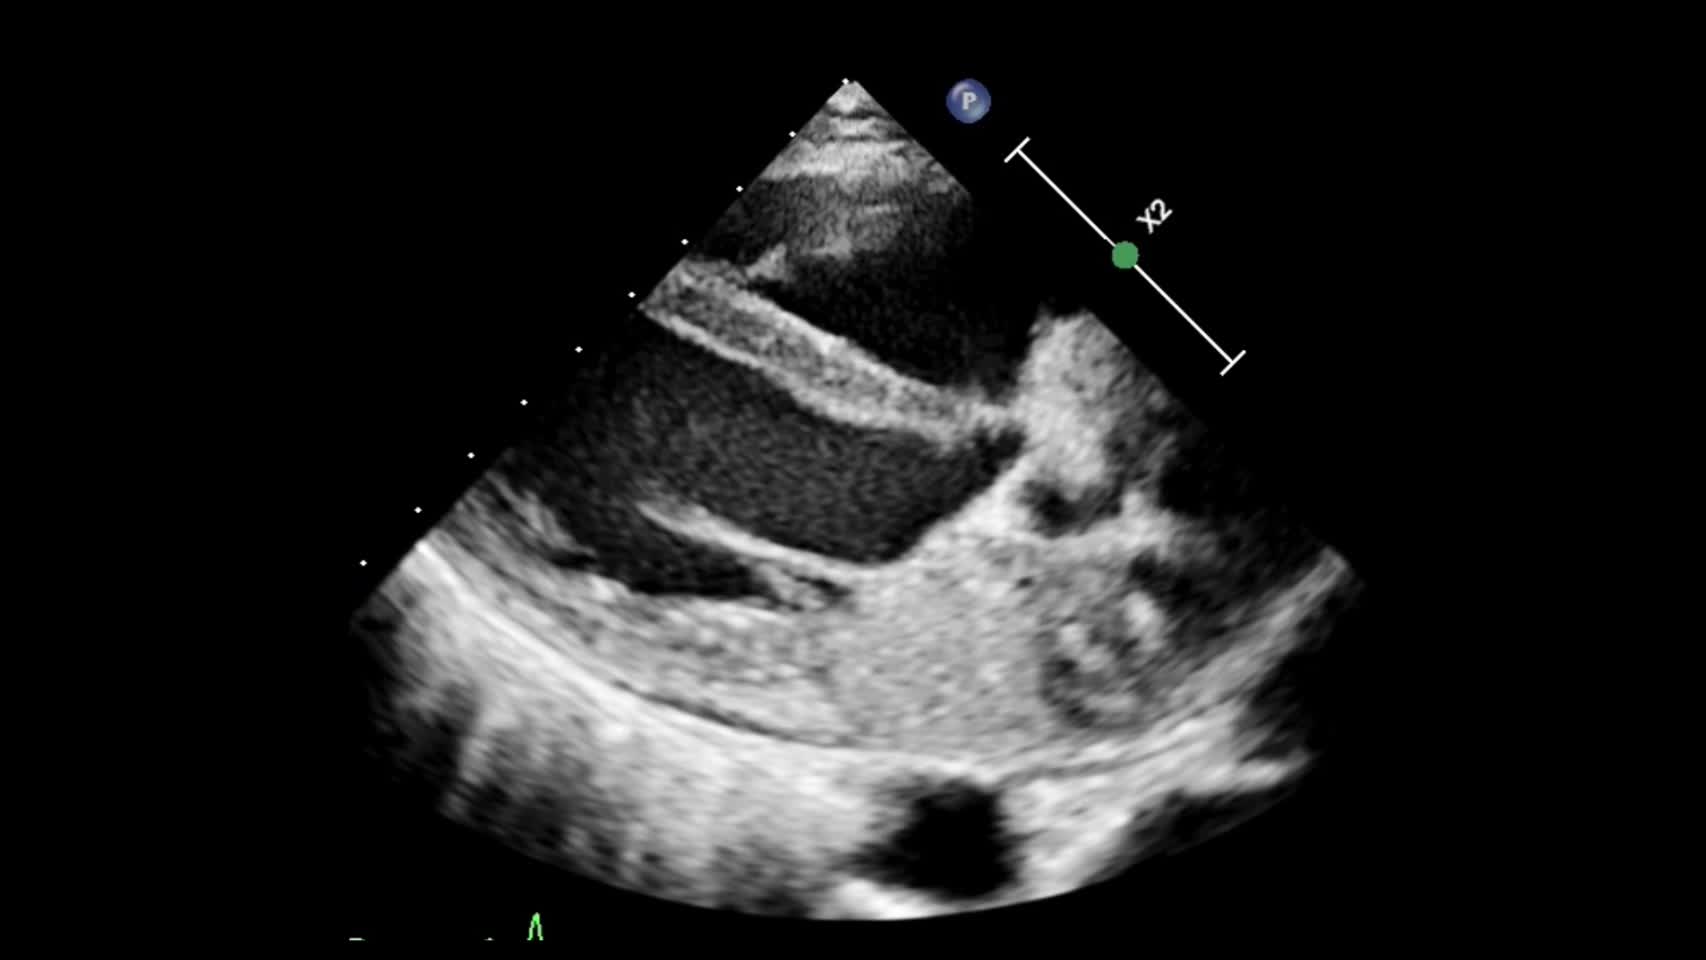

動画20-1 心エコー①(胸骨左縁長軸像)...